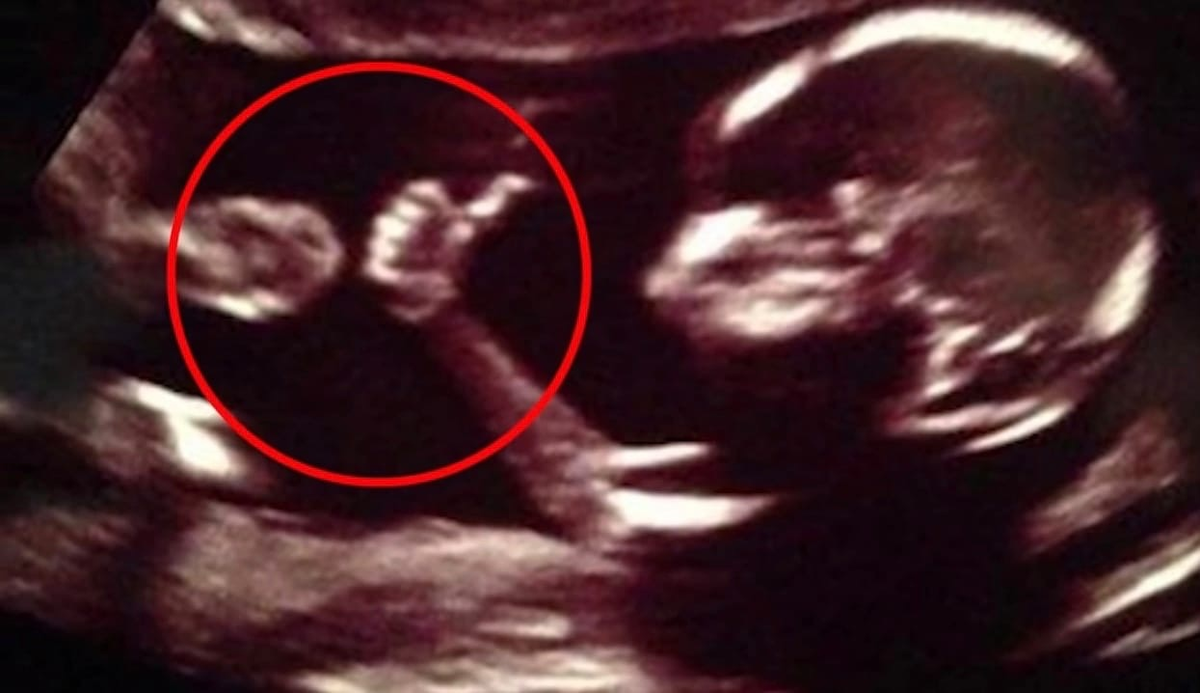

10 детей, которые делали странные вещи во время УЗИ! | Профессор Гуглов ...